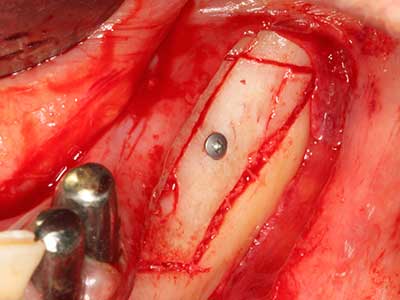

Indicazione: prelievo osseo autologo

I trapianti autologhi dell'osso si eseguono in forma di blocchi, strati e anelli, anche in combinazione con materiali di riempimento tipo microframmenti. Se il sito dell'impianto viene preparato contemporaneamente all'accrescimento, diversi sistemi di filtraggio dell'osso si sono rivelati efficaci per la raccolta dei microframmenti ossei risultanti. Come metodo alternativo, il sito dell'impianto può essere preparato utilizzando un dispositivo a bassa velocità senza irrigazione. Senza l'inserimento di un impianto, è possibile raccogliere i microframmenti ossei dalla periferia mediante bisturi affilati per tessuto osseo. Ciò può essere eseguito anche con la piezochirurgia mediante appositi raccordi che raccolgono microframmenti ossei di qualità più elevata rispetto a quelli raccolti con trapani rotondi, come è stato confermato in uno studio comparativo dei due metodi (Chiriac, Herten et al. 2005).

La piezochirurgia presenta altri vantaggi per quanto riguarda la raccolta di blocchi ossei. Oltre all'elevata precisione dell'osteotomia appena descritta, l'utilizzo di puntine per sega molto sottili permette di minimizzare in maniera significativa la perdita di materiale. È molto probabile che si verifichi una maggiore perdita di materiale durante la raccolta utilizzando puntine di strumenti più spessi, in particolare delle frese Lindemann (Lakshmiganthan, Gokulanathan et al. 2012). La separazione basale, necessaria in particolare per i trapianti di blocchi nella zona retromolare, viene semplificata grazie a seghe specificatamente progettate di forma rettangolare; di conseguenza la piezochirurgia è considerata una procedura precisa, semplice e sicura per la raccolta di blocchi di osso nella zona retromolare (Happe 2007) (figg. 1-12).